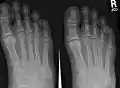

Bones of the right foot. Dorsal surface. Third metatarsal bone is the yellow bone third from the left